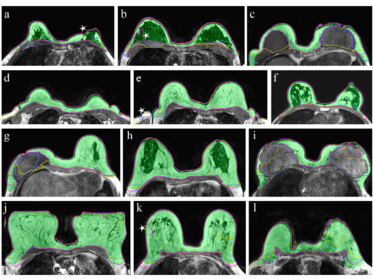

Breast cancer is the most common tumor disease among women. Since there are currently no preventive measures, early detection of tumors through screenings is emphasized. During these screenings, mammography and MRI data are collected.

In Pro-Mics-BrCa, we aim to more accurately predict the risk of tumor development in the following years based on the image data. A low false prediction rate is important to avoid unnecessary procedures like biopsies and to prevent causing anxiety among patients.

Methodologically, we use both classical biomarkers (radiomics) from image data and modern neural networks. An important component is determining risk mutations in breast tissue. Our long-term goal is to provide a toolkit for better prediction of cancer development.